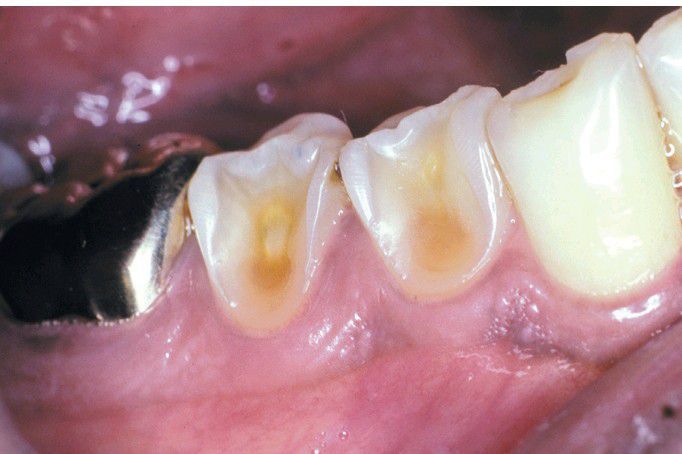

Erosion

Extensive loss of enamel and dentin on the buccal surface of the maxillary bicuspids. The patient had sucked chronically on tamarinds (an acidic fruit)